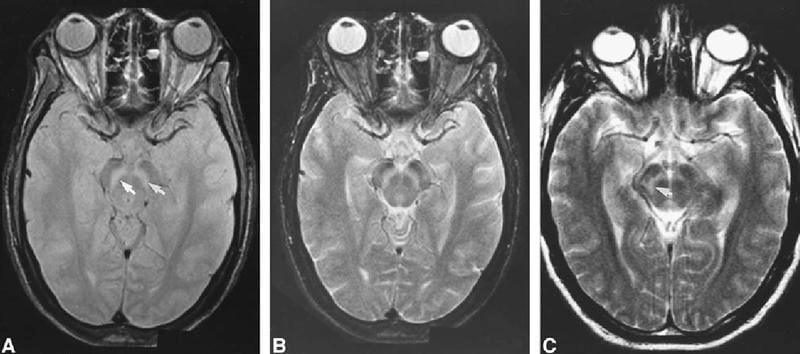

Image of the disease St. Louis Encephalitis